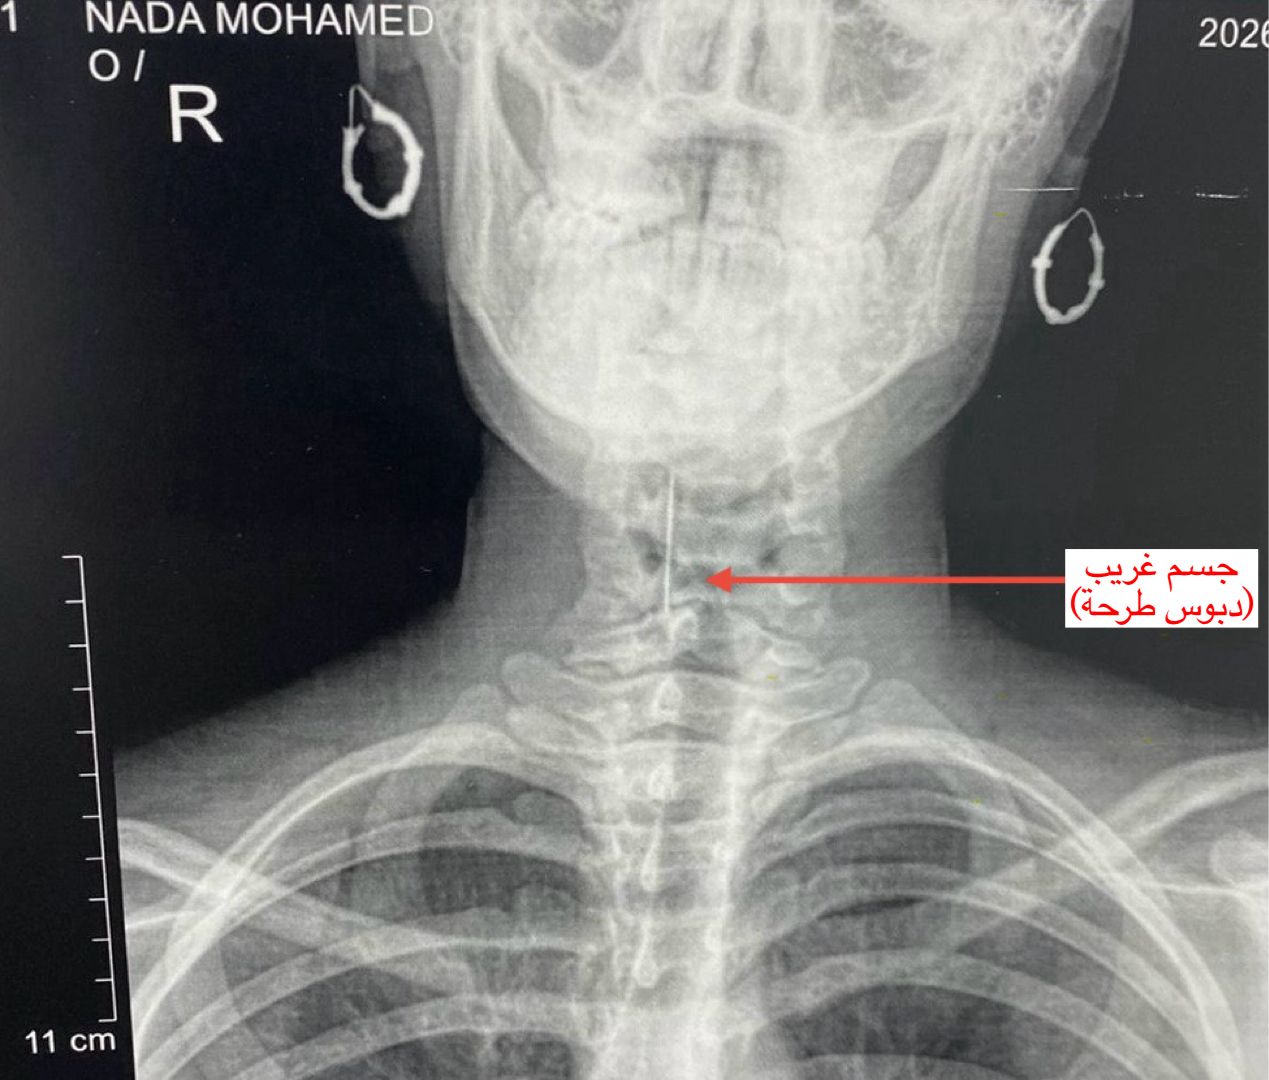

واستقبل قسم الاستقبال والطوارئ بالمستشفى المريضة وهي تعاني من آلام شديدة بالرقبة وصعوبة حادة في التنفس، حيث جرى على الفور إجراء الفحوصات والأشعة اللازمة التي كشفت عن استقرار الدبوس في منطقة دقيقة بمدخل مجرى التنفس، ما شكّل خطورة على حياتها.